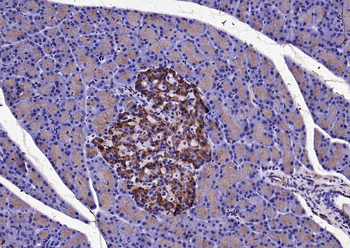

KLK1 Rabbit Polyclonal Antibody

IF, IHC-Fr, IHC-P, WB

应用稀释比例:WB=1:500-2000, IHC-P=1:100-500, IHC-F=1:100-500, IF=1:100-500